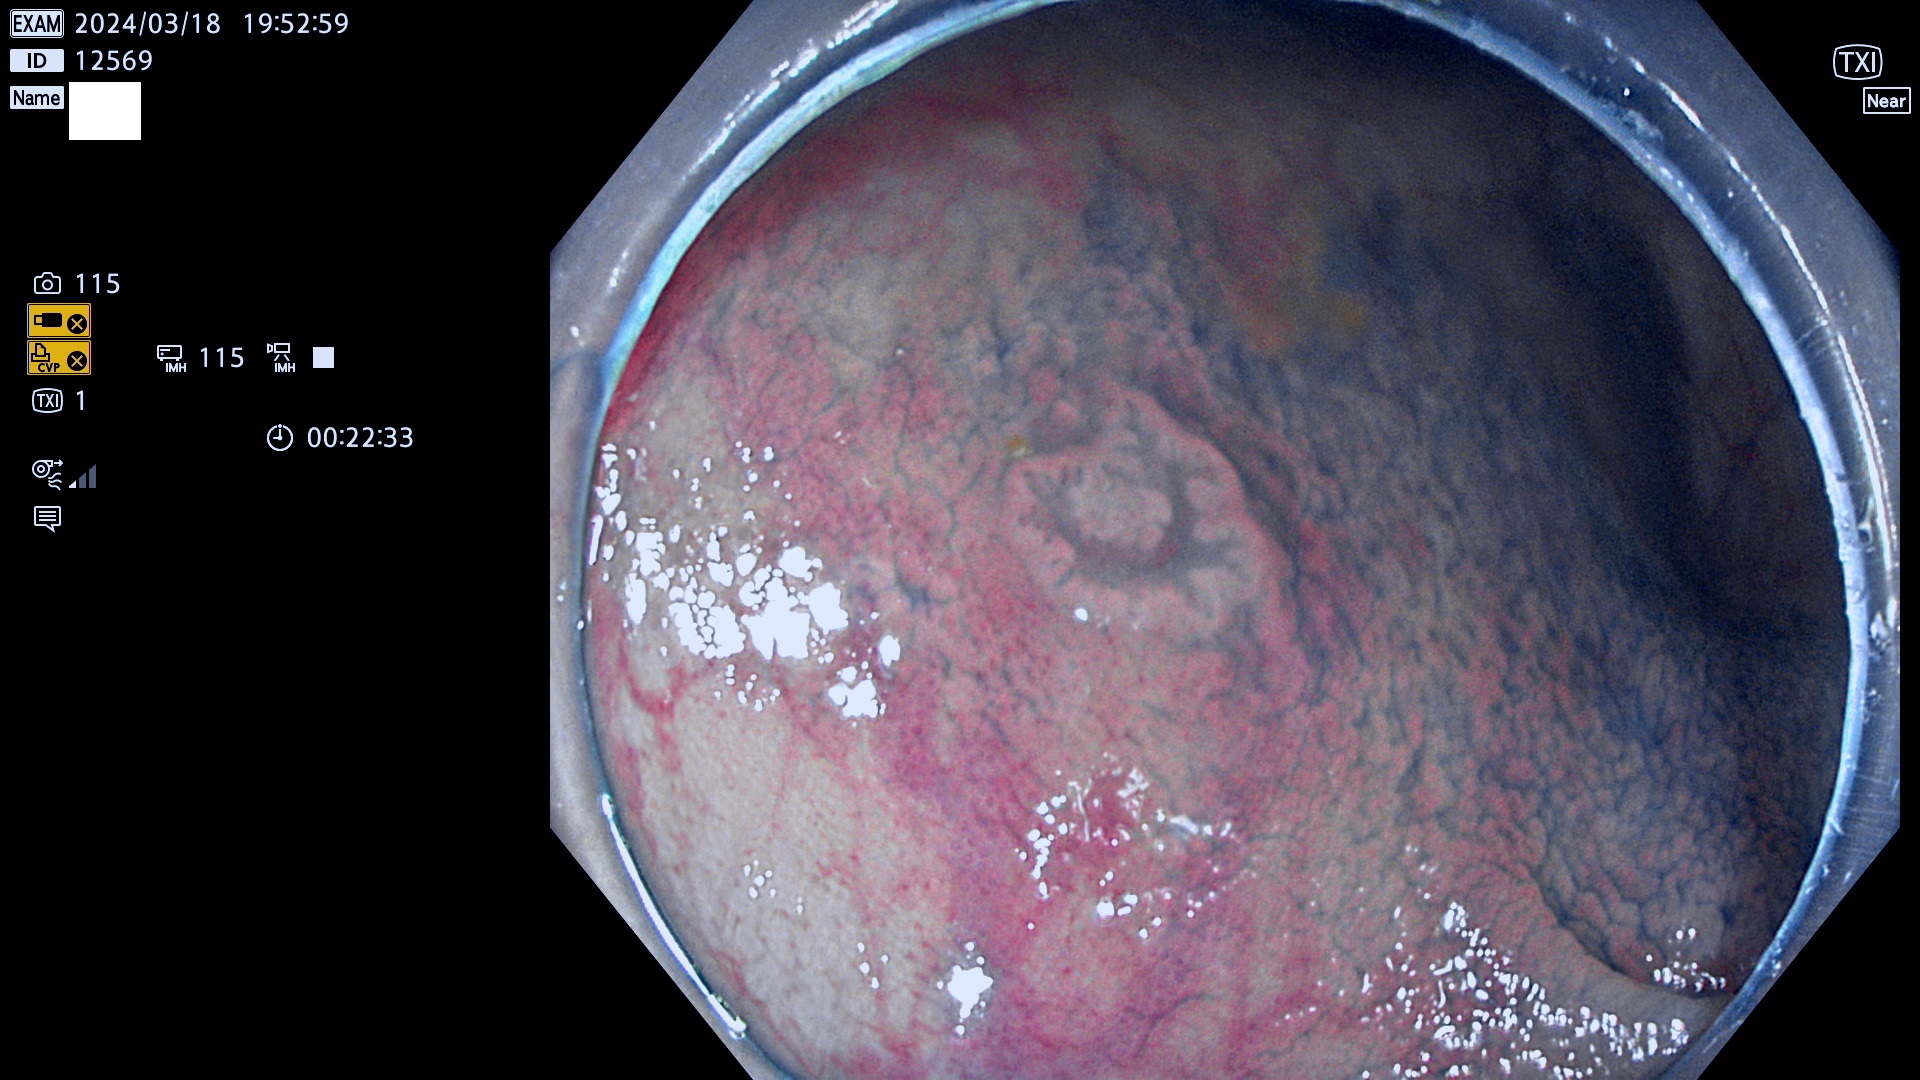

表面型腺腫(Flat Adenoma)の中で、完全に平坦な物をUb、陥凹している物をUcと呼びます。平坦隆起型(Ua)よりも、発見が難しく危険な病変です。

ビランと鑑別の困難な腺腫